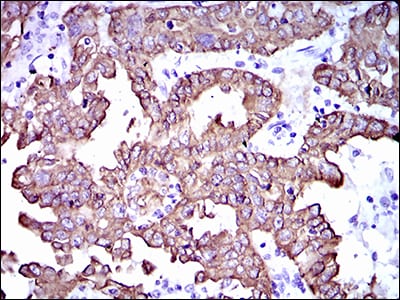

分类: 科研抗体货号: 30512别名: MEMD; CD166; FLJ38514; MGC71733应用: IHC,IF,FCM反应种属: Human